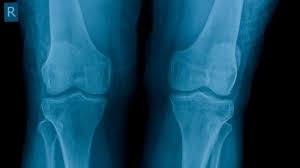

Symptoms-In the early stages, you may have no osteomalacia symptoms, although signs of osteomalacia may be apparent on X-ray pictures or other diagnostic tests. As osteomalacia worsens, you may experience bone pain and muscle weakness.